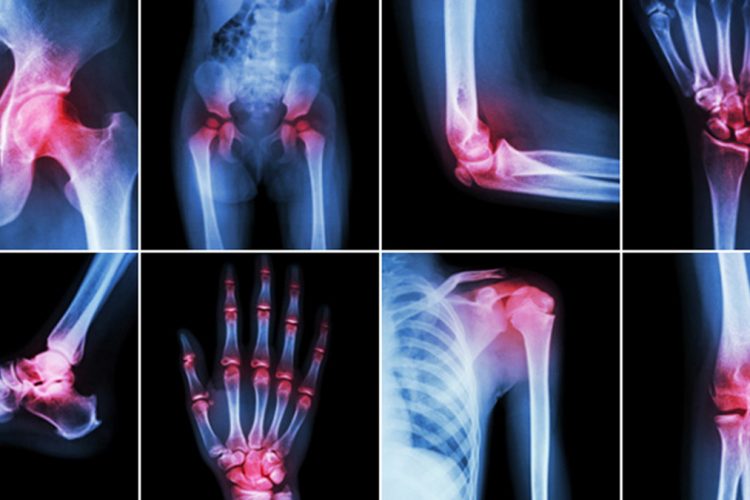

Artriti është një sëmundje inflamatore që prek kyçet.

Kjo sëmundje shkakton shumë dhimbje për pacientin.